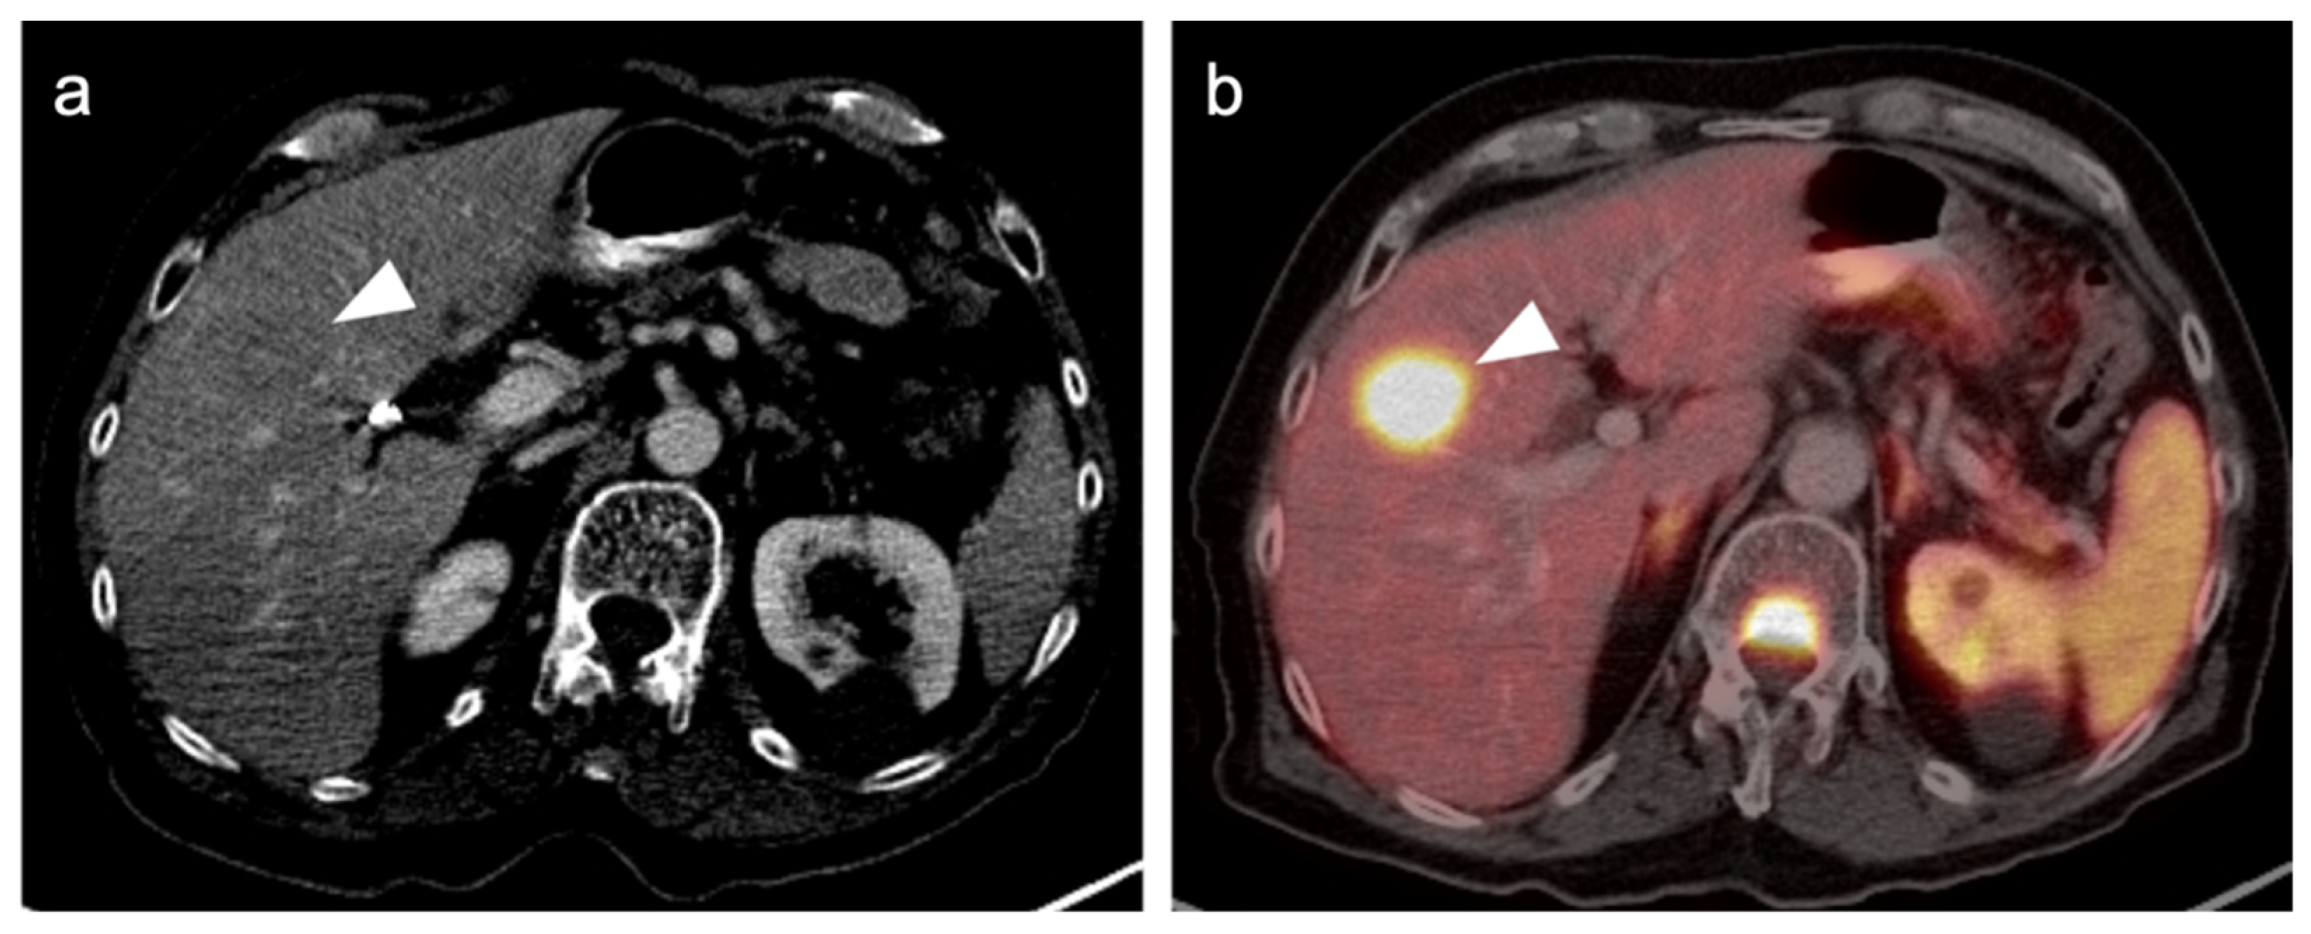

2.3.2. Ocular Melanoma